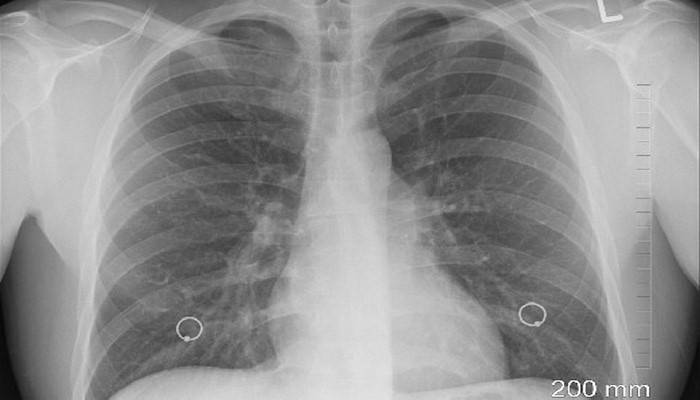

Сообщается, что опухоль может давить на верхнюю полую вену — важнейший кровеносный сосуд в организме человека, по которому кровь доставляется от верхней части тела обратно к сердцу. Но, если кровеносный сосуд блокируется, возможно, из-за увеличившегося злокачественного новообразования в легких, то появляются характерные отеки лица, отмечается в статье.